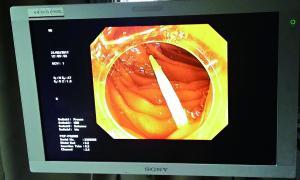

卡在肠道中的牙签的影像检查图。

男子误吞牙签被穿肠破肚

今年初,广州一名三十多岁的男子和一群朋友喝酒。谁知喝得痛快,一不留神把杯中的牙签咽了下去。隔了两天,他因肚子剧痛就诊,当时白细胞指标已飙高到18000单位以上,提示体内有严重的感染。

据中山一院胃肠外科谭进富副主任医师介绍,胃镜检查发现,这根牙签一路下滑,滞留在小肠,一端刺破肠道,钻出去的部分占了三分之二长,引发了严重感染。